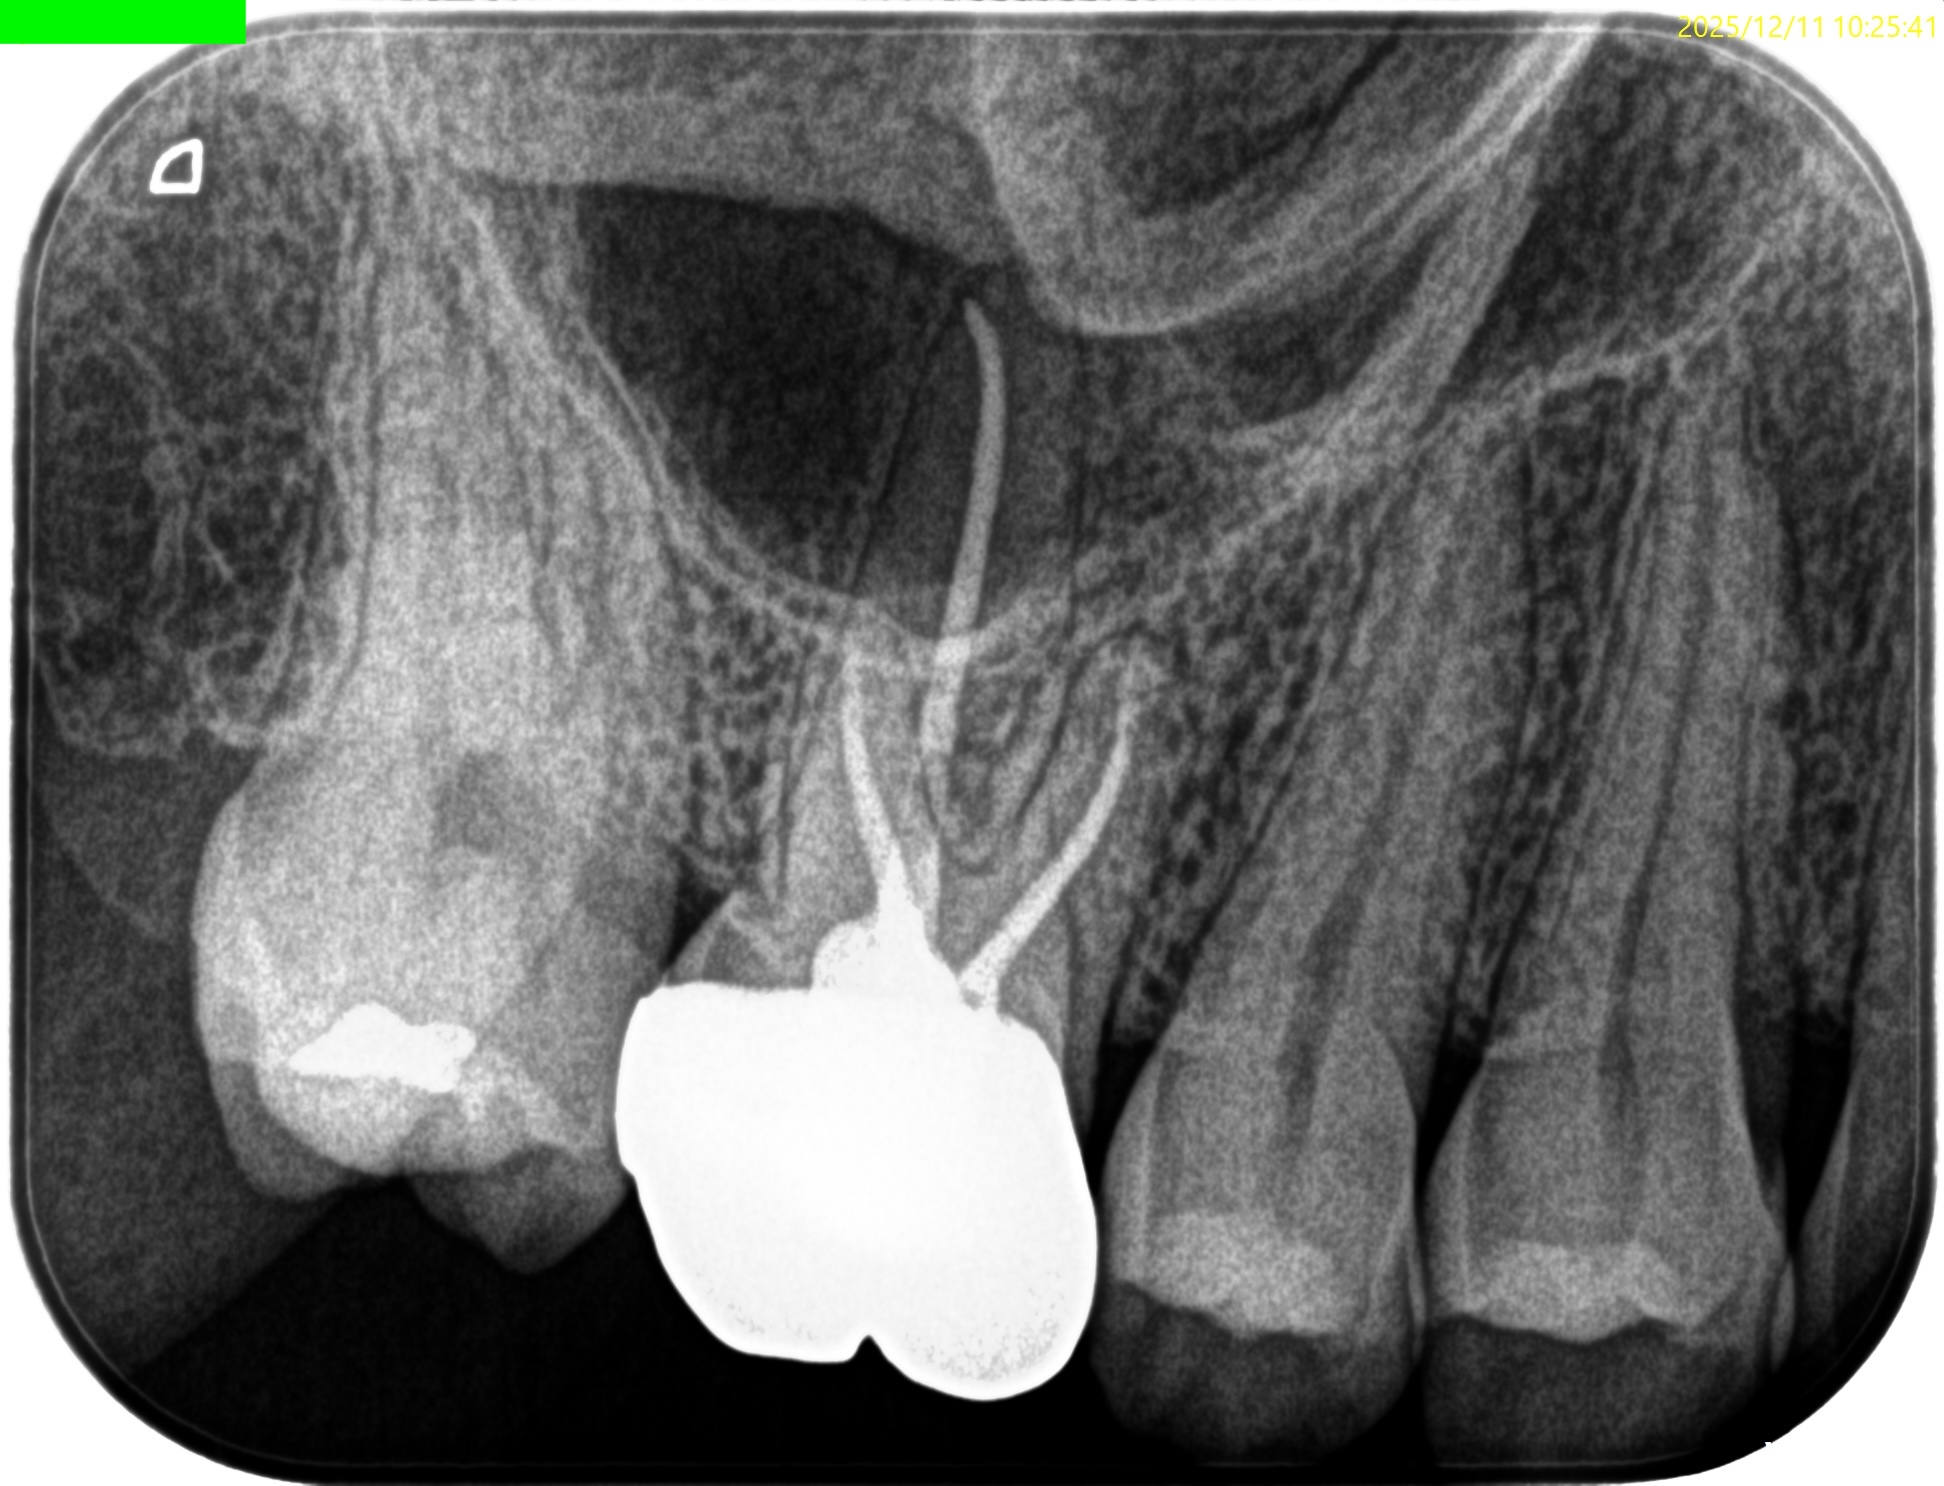

#3 RCT 1yr recall(2025.12.11)

PA, CBCTも撮影した。

MB

DB

P

初診時と比較した。

はみ出たBC sealerが消失して歯槽骨と置き換わっている

という臨床的事実だ。

このケースではみ出たBC sealerが歯槽骨に置き換わったのか?私にはわからない。

が、根尖病変が治癒し歯槽骨に置き換わったのは紛れもない事実だ。